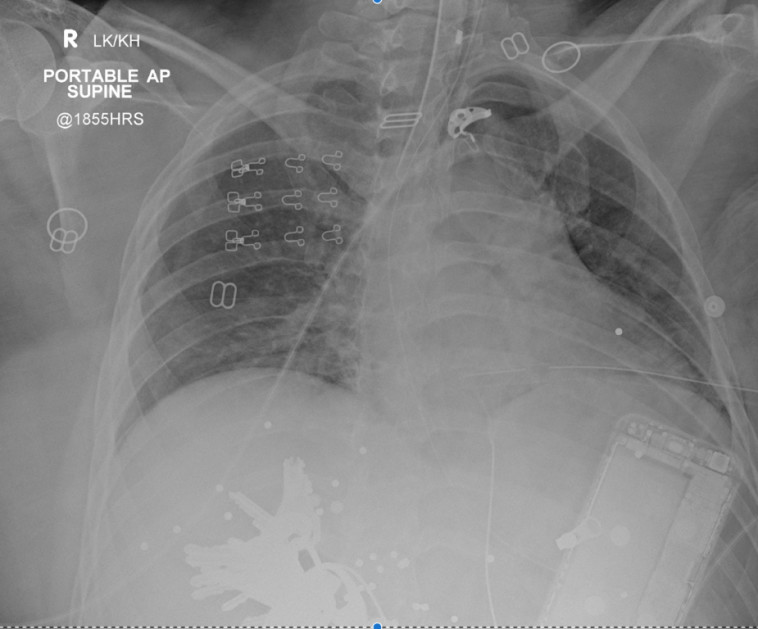

מבדיקה מעמיקה יותר, התברר שהברזל סיבך ואף החמיר את מקרה, לאחר שנדחף לתוך גופה של האישה מעוצמת הפגיעה של הקליעים. הוא חתך את את בטנה של האישה לשניים, חתך את הכבד שלה, פגע באבי העורקים וקרע את הסרעפת שלה: "לא האמנתי לחדות של הקצוות שלו, הברזל פעל במקרה הזה כמו חרב, זה היה כמעט כירורגי". היא סיכמה את המקרה המפתיע: "עבדתי במקצוע הזה כבר 20 שנים, אבל בחיים לא הייתי מעלה על דעתי שחוט ברזל של חזייה יוביל למצב מסכן חיים"

Canadian Journal of Anesthesia :צילום נטגן של האישה הפצועה. צילום